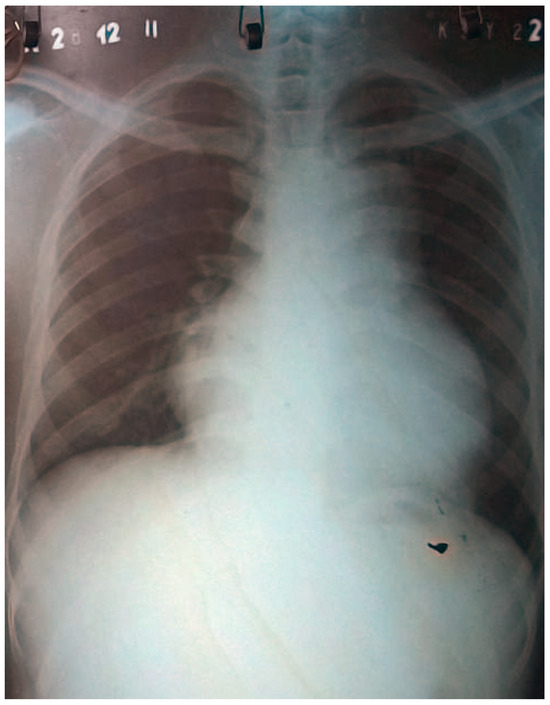

Surviving Acute Traumatic Transection of the Ascending Aorta and Proximal Aortic Arch

We report a 22-year-old male patient who survived clinically unapparent acute traumatic transection of the distal ascending aorta and the proximal aortic arch. Two months after the incident, the patient presented with hoarseness, respiratory distress and severe venous congestion of the upper part [...] Read more.

We report a 22-year-old male patient who survived clinically unapparent acute traumatic transection of the distal ascending aorta and the proximal aortic arch. Two months after the incident, the patient presented with hoarseness, respiratory distress and severe venous congestion of the upper part of the body. Echocardiography demonstrated a huge mediastinal tumour, dilated right heart chambers as well as pericardial tamponade. In the computed tomography (CT), scan rupture of the distal ascending aorta and the proximal aortic arch was found. The preserved adventitial layer, preventing immediate death from exsanguination or pericardial tamponade, distended over time forming a false aneurysm with a diameter of 9 cm, with its main part being located to the left of the trachea. Systolo-diastolic motion of the thin-walled false aneurysm led to the typical pulse-synchronous horizontal motion of the thyroid cartilage and the trachea, described as the Cardarelli sign. As a result of systolic expansion and diastolic shrinking of this huge false aneurysm, the arterial blood pressure curve of the patient perfectly imitated the blood pressure curve seen only with a properly timed intra-aortic balloon pump. In addition, the systolic blood pressure repeatedly compressed the main pulmonary trunk, which crossed the bottom of the false aneurysm, consecutively leading to clinically apparent right heart failure, serous pericardial effusion and pericardial tamponade. The patient successfully underwent ascending aortic and proximal aortic arch replacement using deep hypothermia, circulatory arrest and selective antegrade cerebral perfusion. Full article

Show Figures

Figure 1